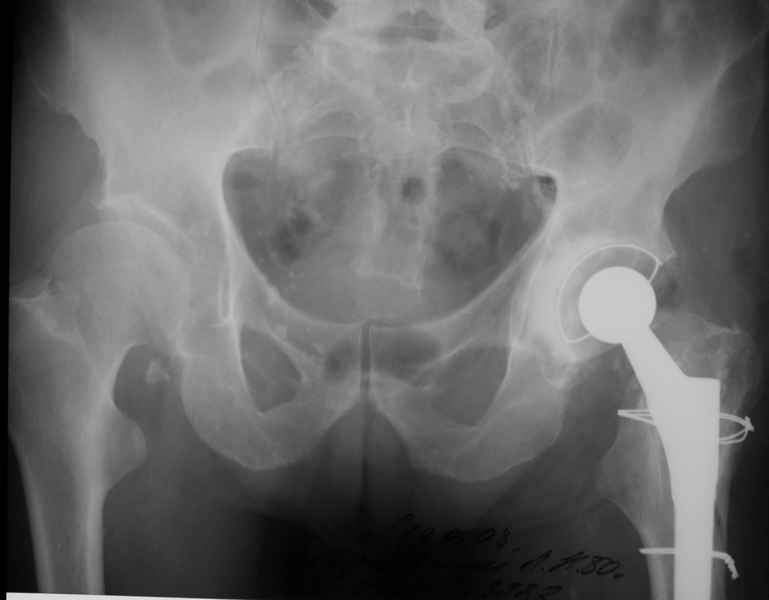

Уважаемые коллеги, продолжая дискуссию, начатую на "Вреденовских чтениях", хочу сказать, что принципиально сущестует два возможных варианта лечения.

1.Остеосинтез на ножке. Мне кажется, что применительно к этому случаю малоперспективный вариант. Синтез хорош, когда можно его выполнить в малоинвазивном исполнении и достигнуть стабильности. Действительно, если ножка б/цементной фиксации после этого не будет иметь фиксации, то ревизия не будет иметь проблем. В представленном случае стабильность синтеза сомнительная, а проведение доп.иммобилизации приведет к контрактуре суставов.

2. Применение ножки дистальной фиксации, мы отдаем предпочтение ножке Вагнера с фиксацией проксимального отдела на ножке. Более травматичное вмешательство, но при стабильной фиксации ножки реабилитация идет в обычном режиме.

Хочется показать два подобных случая, П-ка З. 72 лет и п-т Г. 80 лет. Сразу принимаю замечание, что это были ножки цементной фиксации, просто под руками не было бесцементника.

С уважением, Р.Тихилов